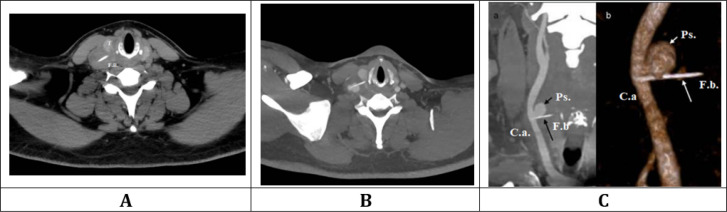

Carotid complications resulting from extra-luminal migration of ingested foreign bodies (FB) are rare but potentially life-threatening. Previous data on the topic predominantly comprises isolated case reports, leaving a gap in comprehensive evidence necessary to guide clinical decision-making. In this article, we offer a narrative review alongside a novel case report, aimed at providing a broad, evidence-based perspective on the topic to guide clinical practice. The search strategy employed keywords related to carotid artery complications from ingested FB across the following electronic databases: PubMed, Scopus, Google Scholar, and Cochrane Central. Screening involved standardized data extraction by two independent reviewers, with a focus on abstracts meeting inclusion criteria and excluding non-English literature and non-relevant studies from further analysis. Moreover, we present a novel case report on the topic that was successfully managed using a unique surgical approach. Overall, a total of sixteen case reports were finally included, data on clinical presentations, diagnostic strategies and findings, surgical management and outcome were extracted, tabulated, and discussed. In carotid complications from extra-luminal migration of ingested FB, high clinical suspicion is crucial due to potentially mild symptoms and negative first-level examinations. Computed tomography (CT) scan plays a pivotal role for accurate diagnosis and surgical planning, along with neck ultrasound to detect complications. Tailored surgical strategies based on the severity of carotid involvement, including venous patch grafts in severe vessels involvement, are crucial for optimal patient outcomes. As a novelty, in our case report, carotid shunt was successfully employed instead of prolonged carotid clamping to reduce the risk of associated neurological sequelae. It could be concluded that, diagnosis and managing carotid complications from extra-luminal migration of ingested FB remains challenging and a multidisciplinary approach is warranted.